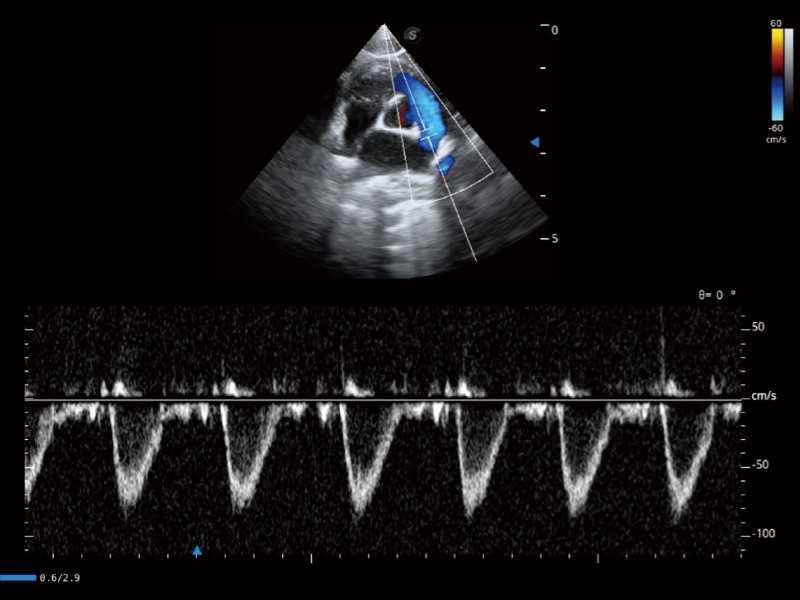

通過(guò)360度任意調(diào)節(jié)3條M型取樣線,在同一心動(dòng)周期上觀察心臟不同位置的運(yùn)動(dòng)曲線,得到準(zhǔn)確的心功能測(cè)量數(shù)據(jù),有效評(píng)估心肌運(yùn)動(dòng)及左心室功能。